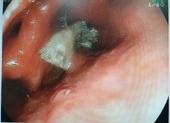

Bác sĩ nội soi lấy răng giả nằm trong dạ dày bà cụ. Ảnh: BVCC

Các bác sĩ tiến hành nội soi can thiệp dùng dụng cụ (snare ) lấy ra bốn chiếc răng giả trong dạ dày bệnh nhân chỉ với 3 phút.